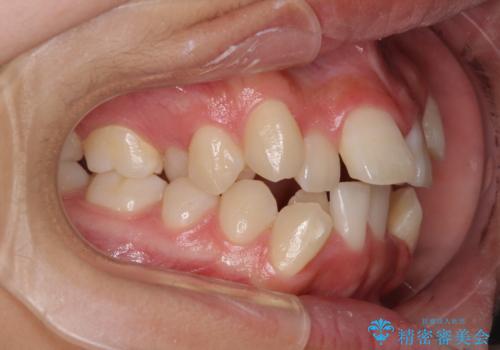

- 歯列全体の叢生を気にして来院された患者様です。

検査を行った結果、上顎骨の横幅が相対的に狭いことが分かり、叢生が強いことから、急速拡大装置にて上顎骨を側方に拡大することで、叢生の解消と奥歯の咬み合わせ改善を図ることとしました。

一般的には上下左右の第一小臼歯4本を抜歯する必要がありますが、拡大量によっては非抜歯矯正の適用となる可能性があるため、まずは非抜歯矯正で治療を開始し、抜歯が必要と判断された時点で速やかに4本抜歯を行うこととしました。